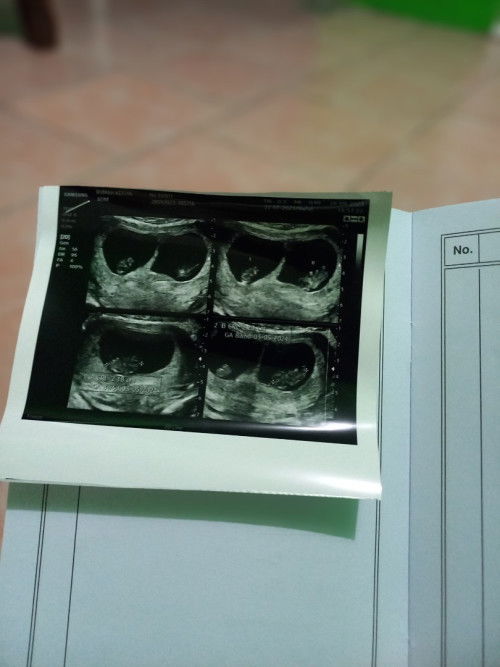

Hamil kembar 2 kantung

Bunda-bunda. Mau tanya, adakah disini yang hamil 2 kantung begini... usia kehamilan saya 11 minggu skg alhamdulillah... Saat usia 7 week usg udah ada 2 kantong dan 2 biji janin di masing² kantung. Ga percaya kn. Akhirnya 3 minggu kemudian usg lagi. Qodarullah, bener ternyata 2 kantung dgn 2 janin dan 2 placenta.. . Sekarang lagi di fase, hormon emodi ga stabil + hormon makan juga ga stabil.. Random banget. . Awalnya ketawa² bareng muridku. Tiba² mual muntah . Padahal ga ngerasain apapun.. Hmm.. Sekarang² badan cpt cape nafas jadi cepet pengap. Tp perut masih rata.. Jadi khawatir.... . Mudah²an ada yg sama yaa.. Doakan sehat² ya kami semuaaa